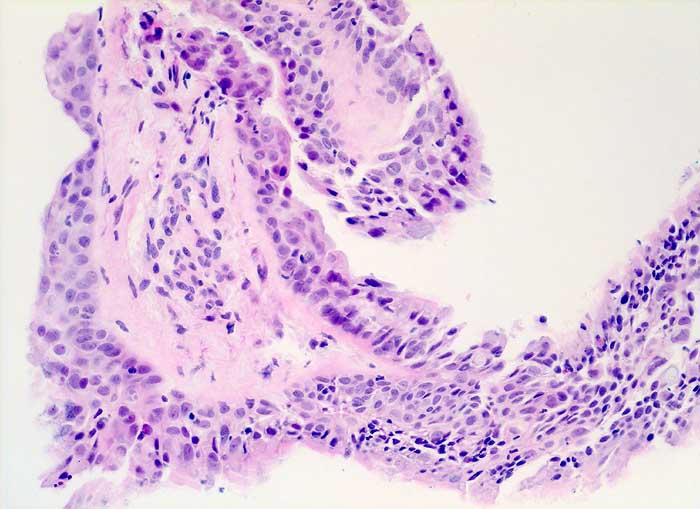

Nach Strahlentherapie eines mediastinalen Tumors oder eines Bronchuskarzinoms zeigen Bronchial- und Alveolarepithel ähnliche Kernveränderungen wie nach Zytostatikatherapie. Die Flimmerzellen haben unterschiedlich stark vergrösserte oft hyperchromatische und entrundete Kerne, sowie fragiles Zytoplasma. Der Nachweis von Flimmerhaaren und die erhaltene Kern-Zytoplasmarelation sprechen für reaktiv veränderte Bronchialepithelien.